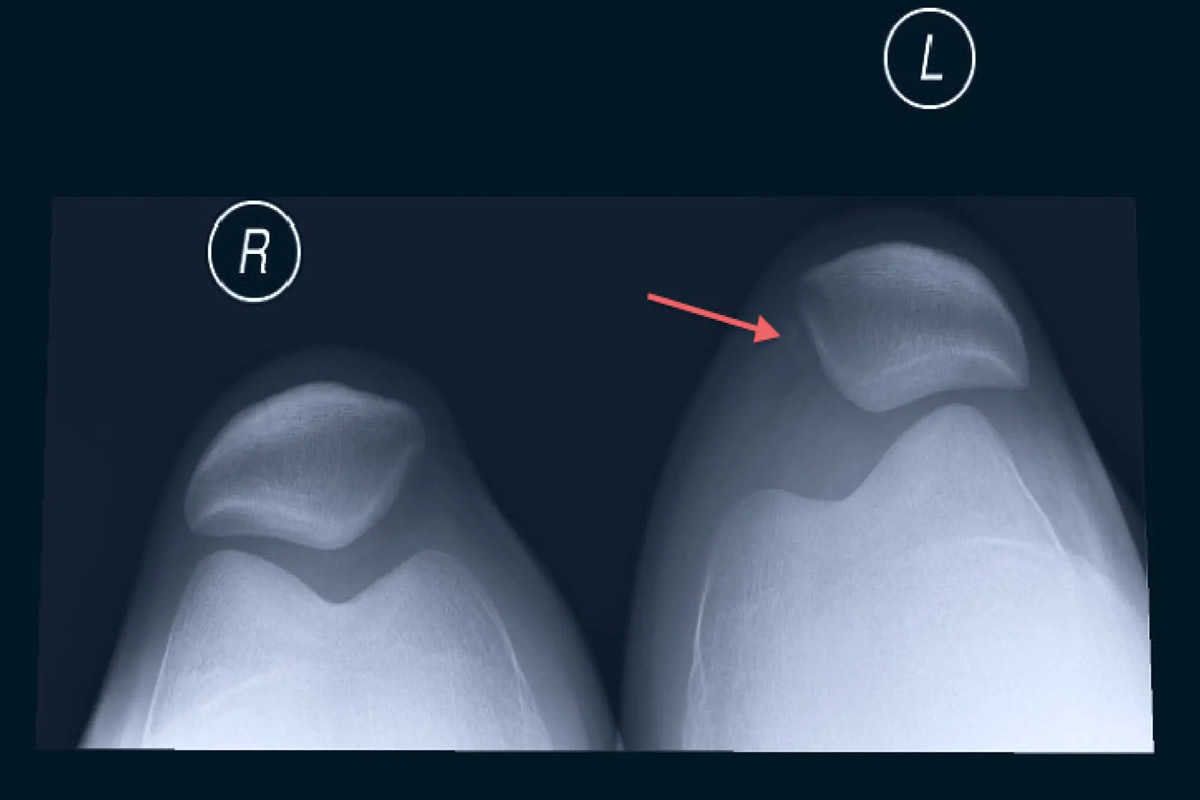

Υπάρχουν συγκεκριμένοι ανατομικοί και λειτουργικοί παράγοντες που αυξάνουν τον κίνδυνο εμφάνισης εξαρθρήματος. Σε αυτούς περιλαμβάνονται η γενικευμένη χαλαρότητα συνδέσμων, η δυσπλασία της τροχιλίας του μηριαίου, η υψηλή θέση της επιγονατίδας (patella alta), η αυξημένη γωνία Q, καθώς και το ιστορικό προηγούμενου εξαρθρήματος.

Η διάγνωση βασίζεται αρχικά στην κλινική εξέταση, όπου διαπιστώνεται η παραμόρφωση, η ευαισθησία και το αιμάρθρο. Οι ακτινογραφίες γόνατος είναι απαραίτητες για τον αποκλεισμό καταγμάτων και την εκτίμηση της θέσης της επιγονατίδας.